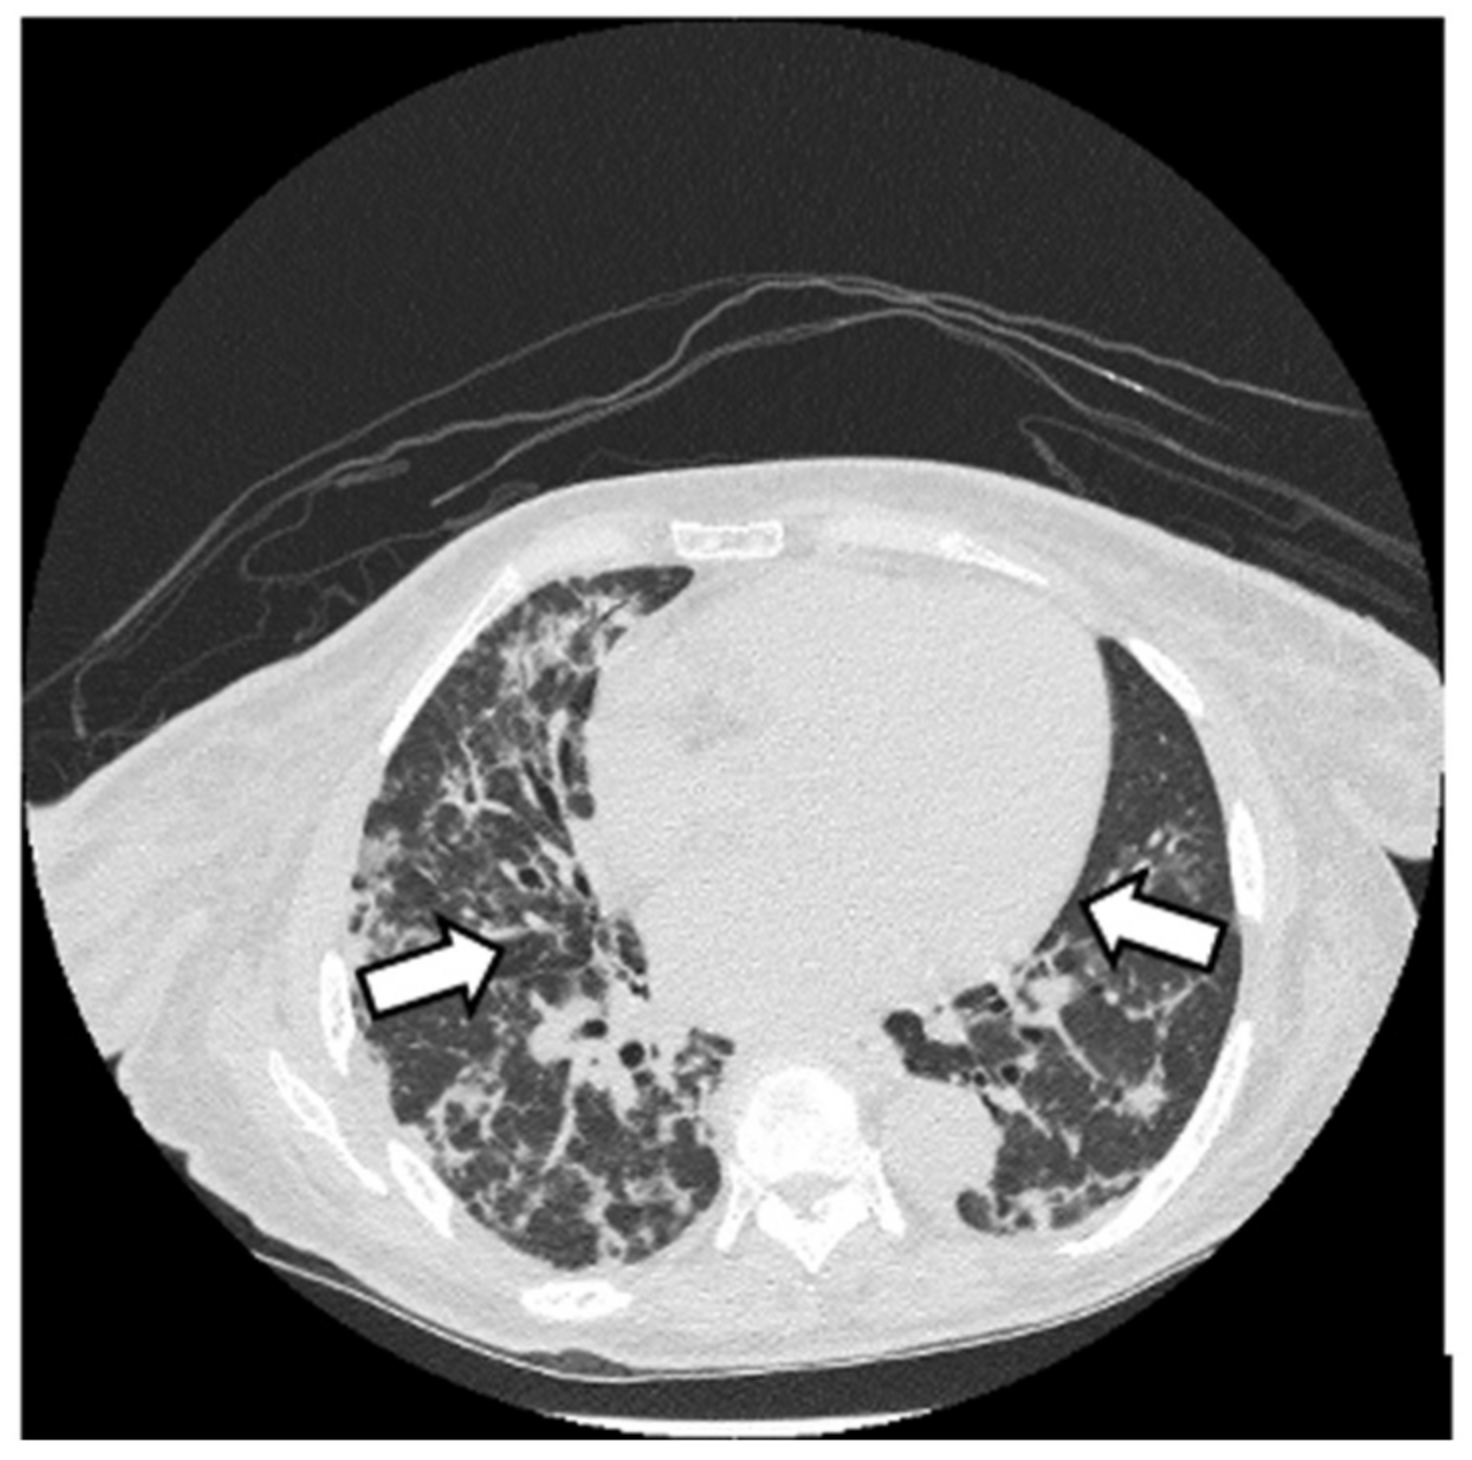

2.2. Case Report 2

6.2. Histopathologic and Radiographic Findings in Myositis-Associated ILD